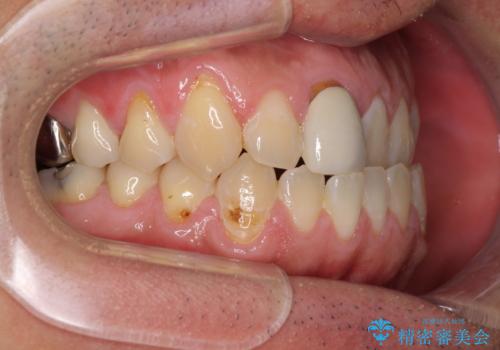

前歯のデコボコとクロスバイトをインビザライン矯正で改善

- 前歯のデコボコと上下のクロスバイトを気にして来院された患者様です。

インビザラインを用い、IPR(歯と歯の間を削る)と歯列全体を拡大させることで、歯並びを整えていくこととしました。